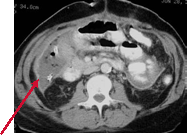

There is a “pad sign” (extrinsic impression) on the loop of bowel in

the RLQ. This is caused by a soft tissue mass impressing the bowel

from outside. The CT shows an abscess from a ruptured appendix.